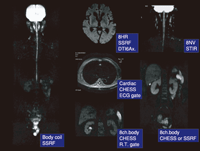

長野市民病院は2007年8月、2台あるMRIのうちの1台を3.0Tに更新した。現在は"Signa HDx"の3.0Tと1.5Tが稼働している。本講演のテーマである拡散強調画像の撮像にあたっては、コイルの選択、脂肪抑制方法の決定、呼吸同期の有無など、非常に多くの組み合わせがある(図1)。そこで今回は、全身の撮像と腹部領域、特に肝臓にポイントを絞ってお話する。

図1

【画像をクリックすると拡大表示します 】